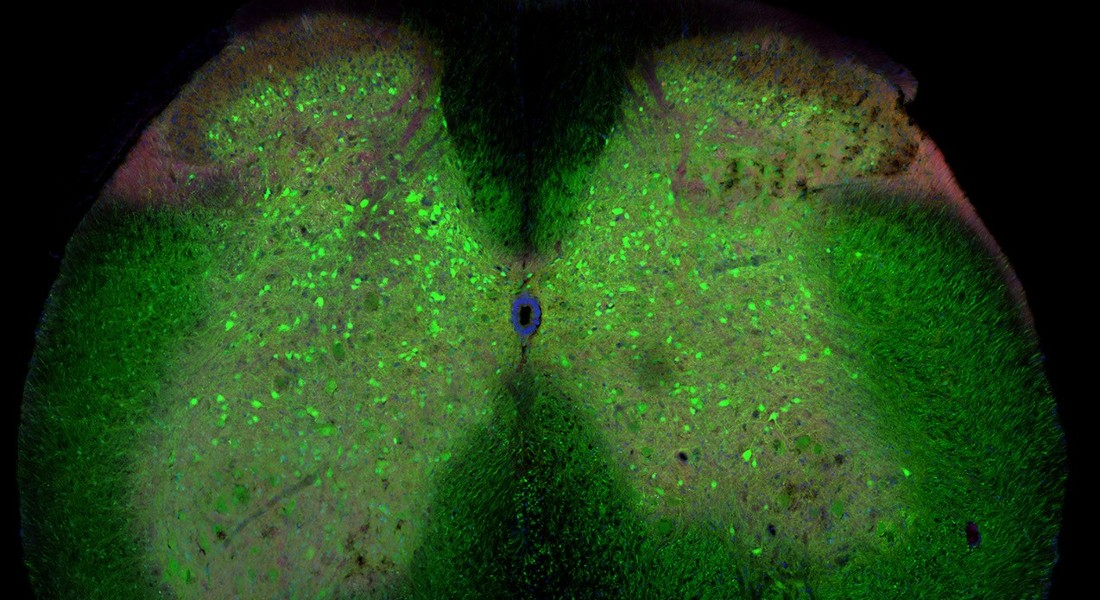

The spinal cord of a mouse with ALS. The green cells are the inhibitory interneurons (Photo: Ilary Allodi) ALS is a very severe neurodegenerative disease in which nerve cells in the spinal cord controlling muscles and movement slowly die. There is no effective treatment and the average life expectancy after being diagnosed with ALS is usually short. Because of this, new knowledge about the disease is urgently needed.